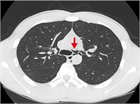

1. 若年でやせ型の男性の胸痛では、特発性縦隔気腫を鑑別診断に挙げることを勧める(推奨度2)

1. 縦隔気腫の誘因となるようなエピソードの後や原因となるような疾患を持つ症例で、胸痛や息切れ・呼吸困難などの症状がみられた場合には、縦隔気腫を鑑別に挙げることを勧める(推奨度2)

1. 胸部X線写真(CXR)で検出しきれない特発性縦隔気腫が少なからずあるため、CXRが正常範囲と判断されても、特発性縦隔気腫が疑われる場合は、積極的に胸部CTを撮影することを勧める(推奨度2)